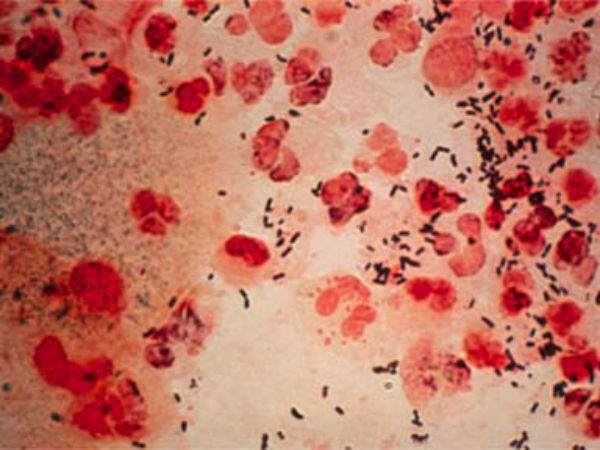

தமிழில் வெட்டை நோய் என்றும் ஆங்கிலத்தில் கொணோரியா(Gonorrhea) என்றும் அழைக்கப்படும் இந்த நோய்தான் இப்போது பீதியை கிளப்ப ஆரம்பித்துள்ளது.

உலக அளவில் பார்க்கையில் ஒவ்வொரு ஆண்டும் புதிதாக பத்து கோடிப் பேருக்கும் அதிகமானோருக்கு இந்த நோய்த் தொற்று ஏற்பட்டு வருவதாக ஐநா தெரிவித்துள்ளது. இது பாக்டீரியாவால் பரவும் நோயாகும்.

இந்த வெட்டை நோய் ஆண்டிபயாடிக் மருந்துகளுக்கு கட்டுப்படுவதில்லையாம். இந்தநோய் விரைவில் குணப்படுத்த முடியாத ஒரு நோயாக மாறி வருவதை கவனத்தில் கொள்ள வேண்டும் என இங்கிலாந்தில் நடக்கின்ற ஒரு மைக்ரோ பயாலஜிஸ்டு மாநாட்டில் எச்சரிக்க உள்ளனர் நிபுணர்கள்.